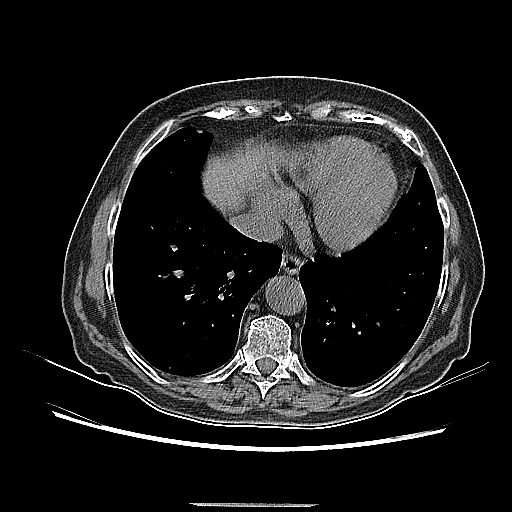

Reconstructed NATIVE CT scan (cycle consistency)

Full window (WL 1023.5, WW 4095 β†’ Low βˆ’1024, High +3071)

Lung window (WL -600, WW 1500 β†’ Low βˆ’1350, High +150)

Mediastinum window (WL 40, WW 400 β†’ Low βˆ’160, High +240)